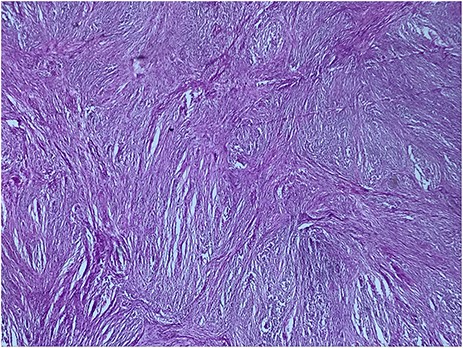

A 73-year-old woman was referred to our general surgery service. Her complain was intermittent gastric discomfort. There was no significant past medical history. There was no history of upper gastrointestinal bleed, or past surgical interventions with no abnormalities found on physical exam. An esophagogastroduodenoscopy (EGD) revealed a submucosal mass in the gastric body. Biopsy of the mass showed no evidence of malignancy. Computerized tomography (CT) scan of the abdomen showed an exophytic solid homogeneous mass along the greater curvature of the stomach and partly projected into the gastric lumen, causing smooth indentation measuring 8 × 8 × 6 cm3 (Fig. 1). The patient’s laboratory results were unremarkable. A presumptive diagnosis of GIST was made. The patient underwent successful wedge resection of the mass through laparotomy and the specimen was sent to pathology. On gross examination, a white intramural, nodular, solid mass measuring 8.7 × 8.8 × 6.7 cm was seen. A cut section revealed whirling trabeculation with a biphasic proliferation of compact hypercellular areas and myxoid hypocellular areas (Fig. 2). Sections from the tumor showed interlacing bundles of spindle cells, which had elongated nuclei, ill-defined cytoplasmic borders and palisading nuclei (Fig. 3). No nuclear atypia was noted. No mitotic activity and no necrosis were identified. There was no lymph node involvement and the surgical margin was negative for tumor cells. A histological diagnosis of a benign mesenchymal tumor was made. Immunohistochemistry (IHC) staining was strongly positive for S-100 (Fig. 4), whereas c-Kit, CD 34; DOG 1; smooth muscle actin (SMA), desmin and AE 1/AE 3 were negative. Hence, a final diagnosis of schwannoma was made. The postoperative period was uneventful and the patient was dismissed from the hospital after 5 days.

Biphasic proliferation of compact hypercellular areas and myxoid hypocellular areas (HE, G x 25)